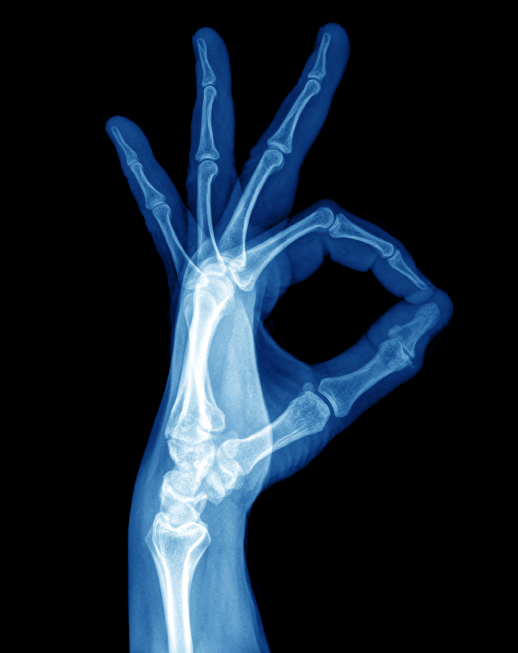

Wilhelm Conrad Röntgen (1845–1923), ein deutscher Physiker, entdeckte im Jahr 1895 zufällig bei der Durchführung eines Experiments die Röntgenstrahlung, die von ihm selbst als X-Strahlen bezeichnet wurde und die medizinische Diagnostik revolutionierte. Doch was genau sind eigentlich Röntgenstrahlen? Die ionisierende Strahlung stellt elektromagnetische Wellen mit Quantenenergien oberhalb von 100 Elektronenvolt (eV) und Wellenlängen unter 10 Nanometer (nm) dar. Im elektromagnetischen Spektrum befindet sie sich oberhalb des ultravioletten Lichts. Röntgenstrahlung entwickelt sich aus der Geschwindigkeitsänderung geladener Teilchen.

In der ersten Phase der Radiologie verwendeten die Ärzte ausschließlich Röntgenstrahlen, später kamen auch weitere ionisierende Strahlungen wie die Gamma-Strahlung hinzu. Die Verfahren dienen der Bildgebung von Organen und Strukturen der Patienten, sodass auch andere bildgebende Verfahren wie die Sonografie oder die Magnetresonanztomografie trotz fehlender Strahlung der Radiologie zuzuordnen sind. Beim Röntgen treten Strahlen durch das Gewebe des Körpers, wobei je nach Dicke, Dichte und Zusammensetzung Strahlungsenergie gedämpft wird – Knochen absorbieren beispielsweise die Strahlung erheblich stärker als Blut. Die durchgängige Strahlung wird mit Röntgenstrahldetektoren aufgefangen, sodass sich ein zweidimensionales Abbild zeigt. Die dargestellten Kontrastunterschiede sind jedoch im Rahmen der klassischen Röntgentechnik relativ gering.